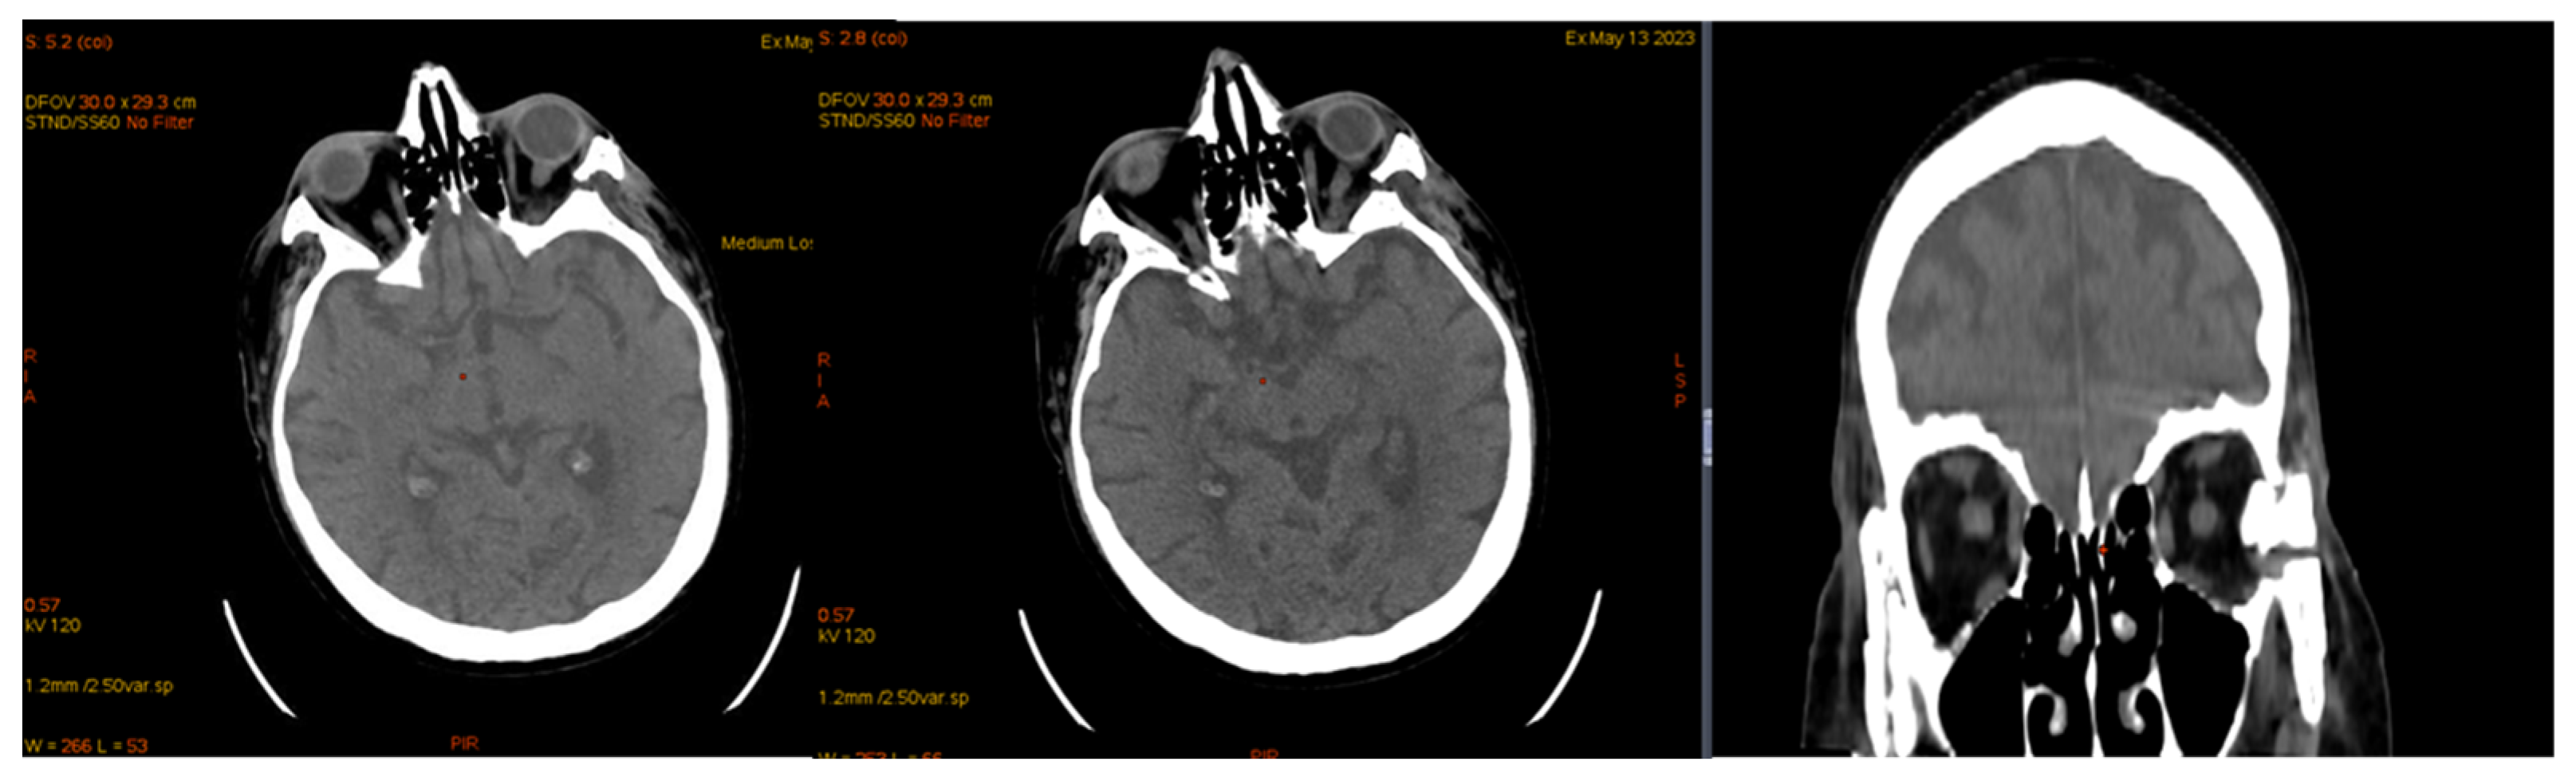

| January 2023 | second extramedullary relapse bilateral ocular left eye clinically, imaging, and biopsy demonstrated right eye demonstrated by imaging | methotrexate, asparaginase, calcium folinate radiotherapy, 30 gy/15 sessions result: imaging complete remission |

| 2 May 2023 | third emr: cardiac and colonic mass (+cns?) | nelarabine+cyclophosphamide+ etoposide |